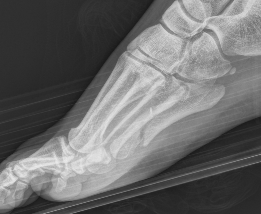

Xray

Zone 3 Fractures

Progression to nonunion of zone 3 fracture with nonoperative care